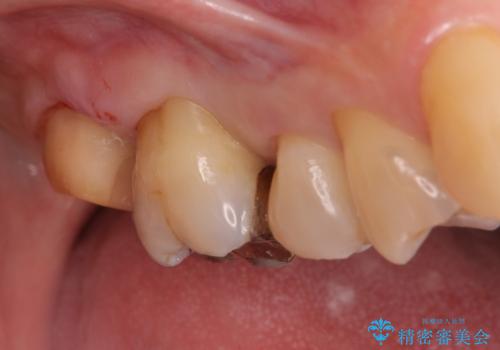

- 冷たいものがしみて飲み物が飲めないとの事で来院。

歯肉が退縮していたので歯周外科手術(歯茎の移植手術)か被せ物で覆う(歯肉退縮しているところまで覆う)の提案をしたところ被せ物がいいとのことでしたので

被せ物の治療のご案内になりました。

適合の良い被せ物が入りました。